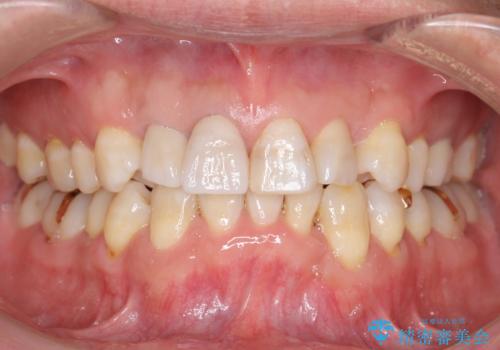

仕上がりに限界はありましたが、比較的短期間で歯並びが整いセラミック治療を行うことができ、患者様に「治療して良かった」とご満足頂けました。

左上1の歯の表面にもともと凹凸とグラデーションがあり、気になるようならセラミックでかぶせるのも一つだと提案しましたがご希望されなかったため、その表面性状を再現して右上1のセラミッククラウンを作製しています。

~被せ物の種類~

右上21:ジルコニアクラウン スペシャル

左上6:ジルコニアクラウン スタンダード

左上7:e-max press セラミックインレー